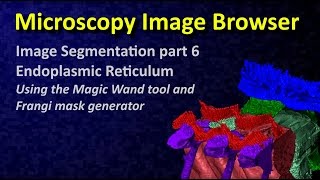

FIJI (ImageJ): Enhancing Contrast of Tubular or Filamentous Structures with Tubeness Filter MIB: Image Segmentation tutorial 6: magic wand and Frangi filter

MIB: Image Segmentation tutorial 6: magic wand and Frangi filter Comparaison of RORPO against Frangi's Vesselness on a Brain MR image

FIJI (ImageJ): Enhancing Contrast of Tubular or Filamentous Structures with Tubeness Filter MIB: Image Segmentation tutorial 6: magic wand and Frangi filter

MIB: Image Segmentation tutorial 6: magic wand and Frangi filter Comparaison of RORPO against Frangi's Vesselness on a Brain MR image